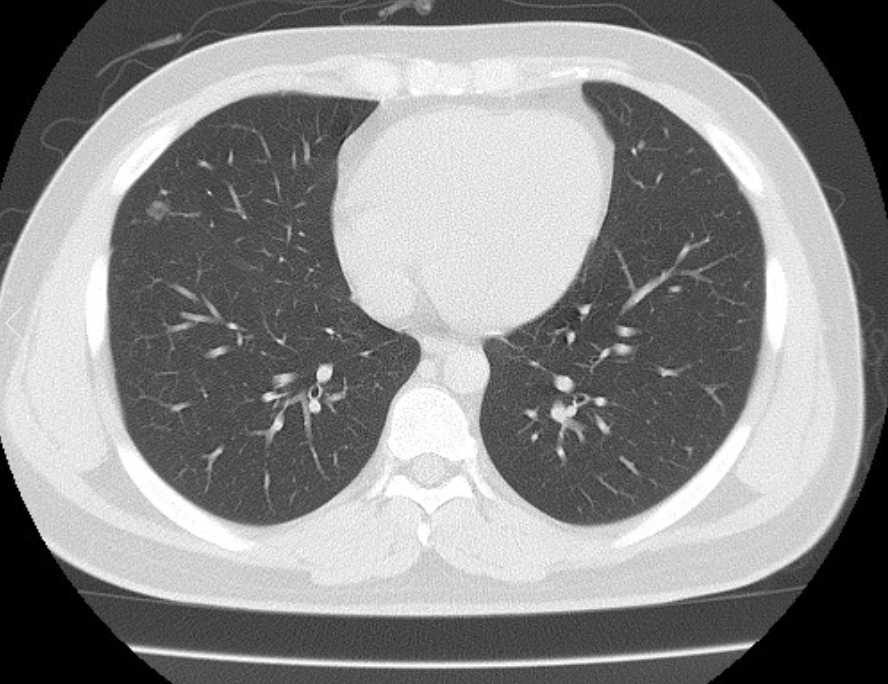

폐ct사진 받았는데 엄청 많더라구요.. 우중엽(40#)에 부분고형결절(6mm, 고형 2mm)결절이 있다고 소견을 받았는데 아래 ct사진 상 위험한 결절로 보이는지 판독좀 부탁드리겠습니다 ㅜㅜ. 다른 사진들 더 많지만 앞뒤 전후로 몇장씩만 가져왔어요..

• 4번 째 사진